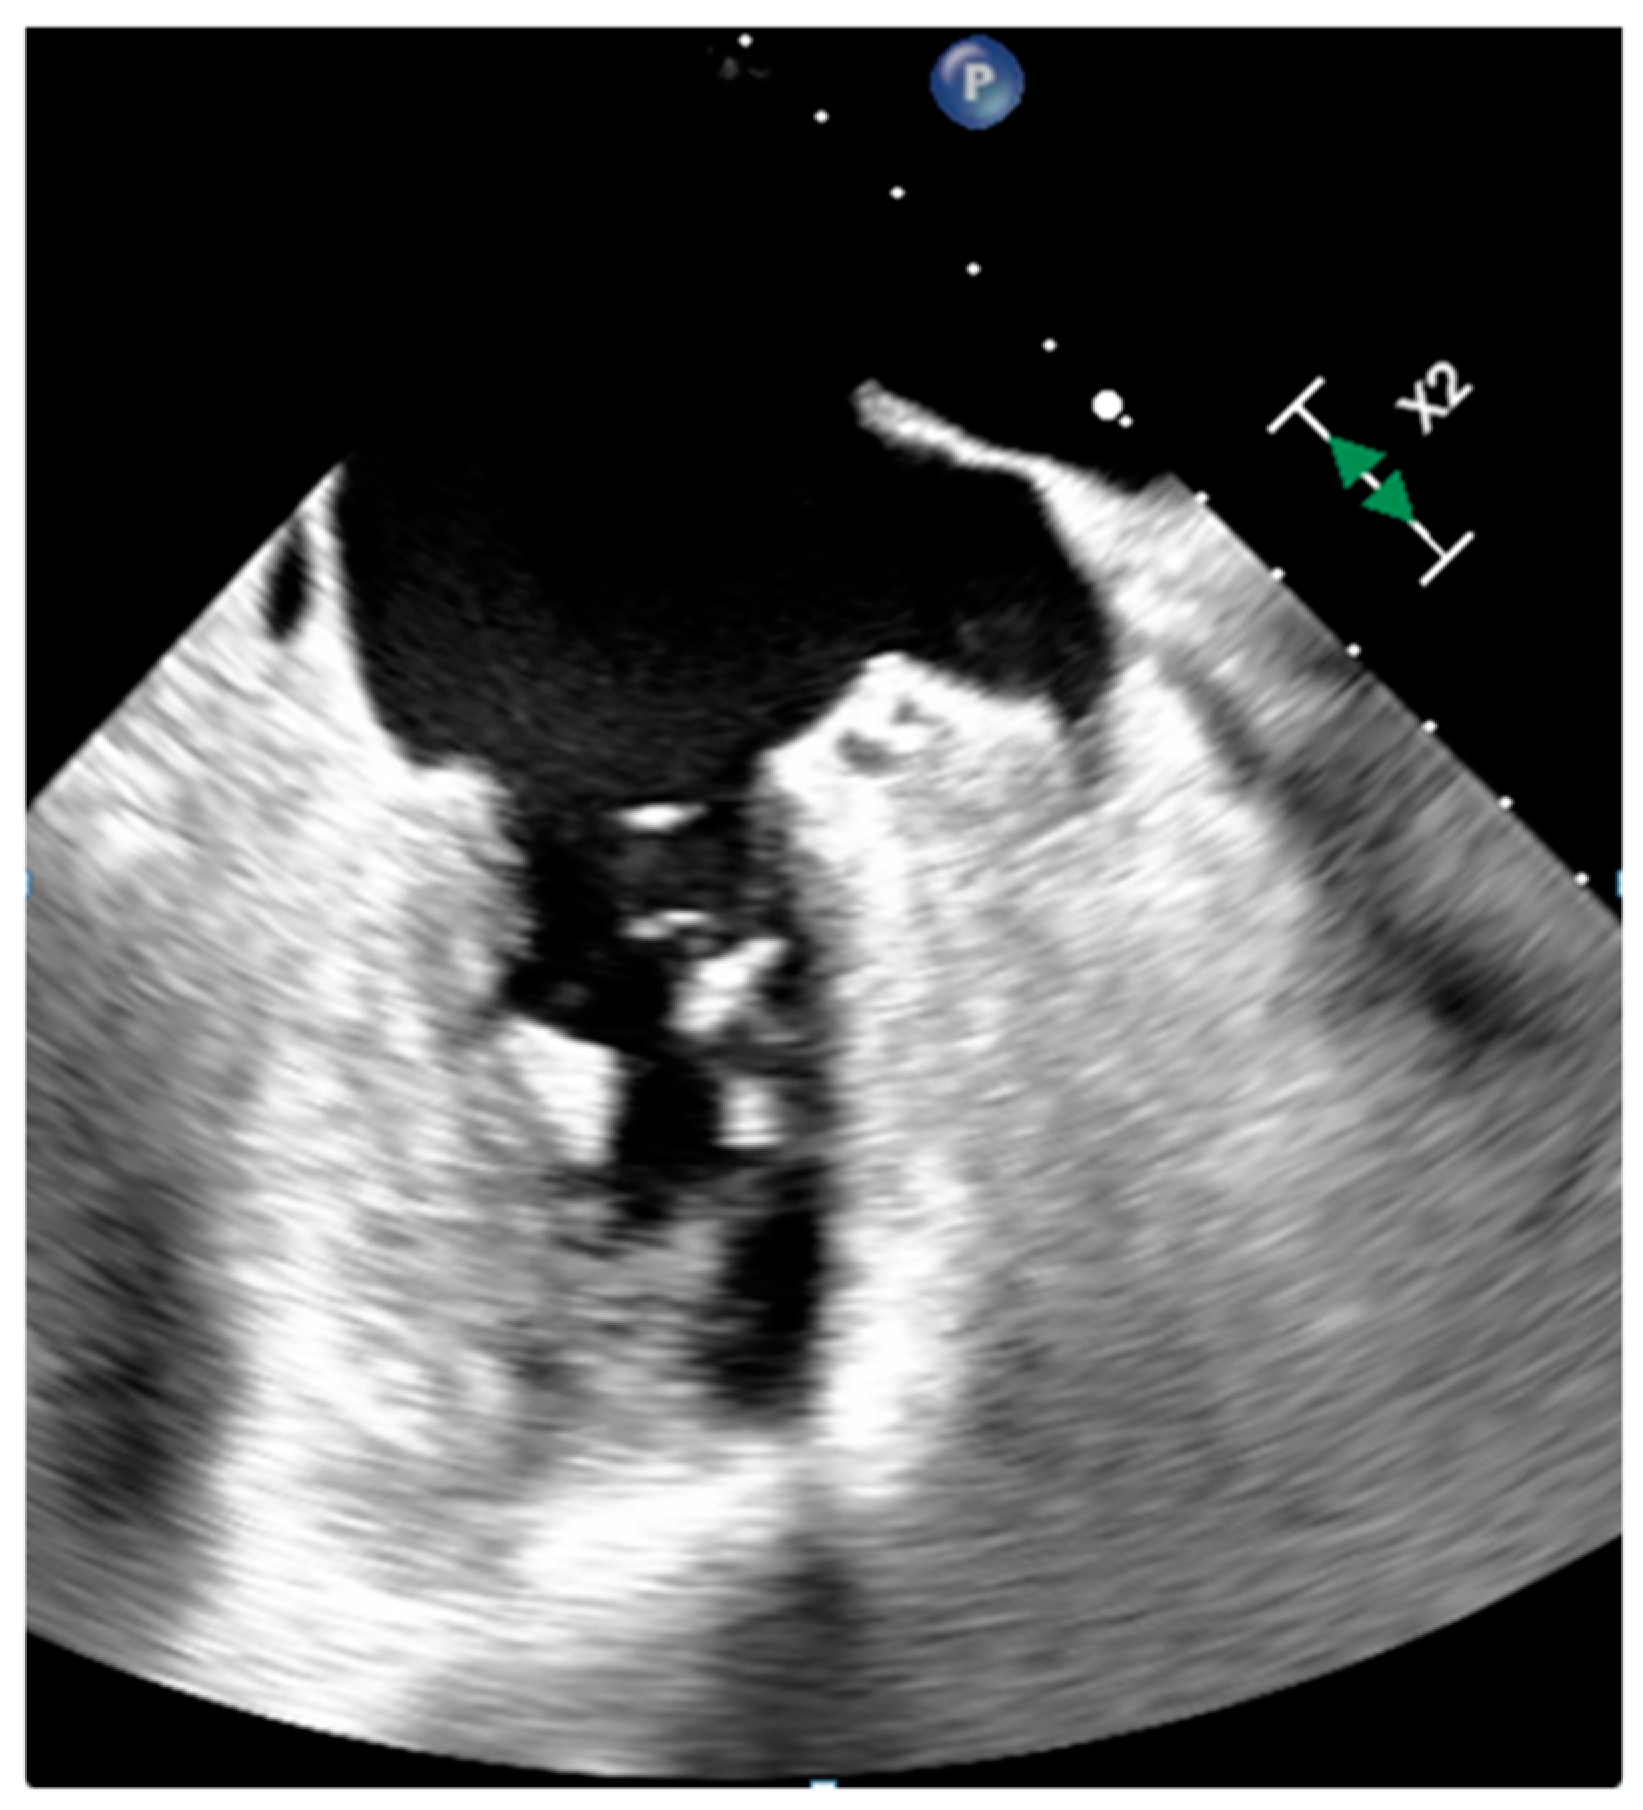

3.1. Thrombus

| Thrombus | Adulthood | LA, LAA (AF) LV (MI) | Asymptomatic, embolic events | Non-enhancing Intracardiac lesion | Acute: Low echodensity, rounded with smooth contours Chronic: High echodensity, linear or crescentic lesions along the endocardial surface | Low attenuation, no contrast enhancement, chronic thrombus may be calcified Usefulness of delayed CT imaging, as in the LAA stasis of blood can simulate a thrombus on early arterial images | Acute: hyper T1w and T2w Subacute: hyper T1w and hypo T2w Chronic: low T1w and T2w No enhancement. |